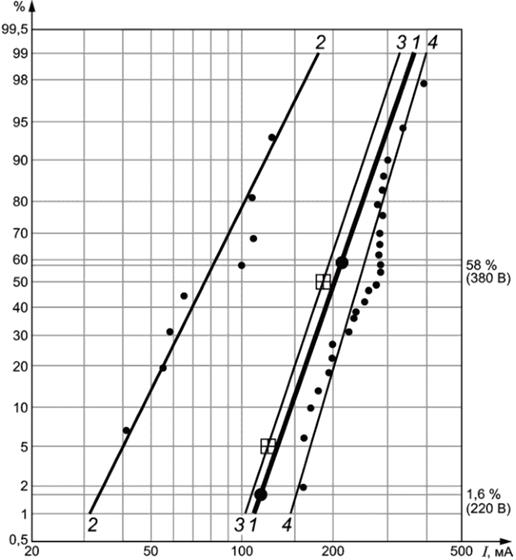

1 - данные по ФЖ для людей, полученные на основе анализа статистики несчастных случаев (UT = 220 В, 1,6%, UT = 380 В, 58%); 2 - данные по ФЖ для собак при длительности протекания тока 5 с; 3 - данные по ФЖ для свиней при длительности протекания тока более 1,5 длительности сердечного цикла; 4 - данные по ФЖ для овец при длительности протекания тока 3 с;

![]() - расчетные данные, полученные на основе анализа статистики несчастных случаев (UT = 220 В, 1,6%, UT = 380 В, 58%, IT = 110 и 220 мА соответственно. Применен коэффициент сердечного тока F = 0,4);

- расчетные данные, полученные на основе анализа статистики несчастных случаев (UT = 220 В, 1,6%, UT = 380 В, 58%, IT = 110 и 220 мА соответственно. Применен коэффициент сердечного тока F = 0,4);

![]() - значения после статистической обработки результатов измерений на свиньях [I (5%) = 120 мА, I (50%) = 180 мА]

- значения после статистической обработки результатов измерений на свиньях [I (5%) = 120 мА, I (50%) = 180 мА]

Рисунок А.18 - Экспериментальные данные по ФЖ для собак, свиней и овец и расчетные данные для людей, полученные на основе статистики несчастных случаев при поперечном протекании тока между кистями рук для напряжений прикосновения 220 и 380 В переменного тока для значений полного сопротивления тела ZT (5%)